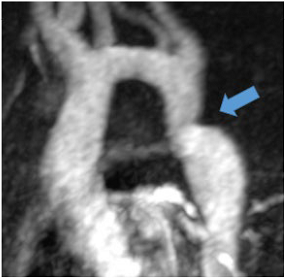

Common non-endocrine causes are aortic coarctation (Table 4N) and renovascular hypertension caused by diseases such as fibromuscular dysplasia (FMD) or renal artery stenosis.

Aortic coarctation is defined as luminal narrowing near the origin of the left subclavian artery and ligamentum arteriosum and is a very rare cause of secondary hypertension with only 0.2% of patients with hypertension affected [82]. Increased afterload due to mechanical obstruction and potential renal ischaemia are regarded as underlying pathomechanisms. CT and, particularly for follow-up, MR angiography are the optimal imaging methods for the detection and quantification of coarctation.

Regarding renovascular hypertension, FMD or renal artery stenosis are the most common causes (Table 4O). Both conditions lead to decreased renal perfusion and subsequent increased systemic blood pressure, but have a different appearance in terms of location: While (atherosclerotic) renal artery stenosis most commonly affects the proximal renal artery, FMD affects the middle segments with alternating strictures and dilatation [83].